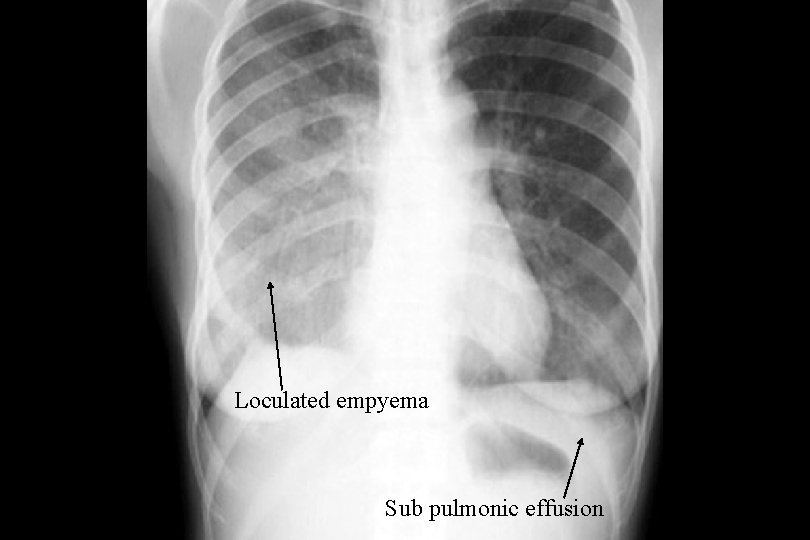

Loculated empyema Sub pulmonic effusion